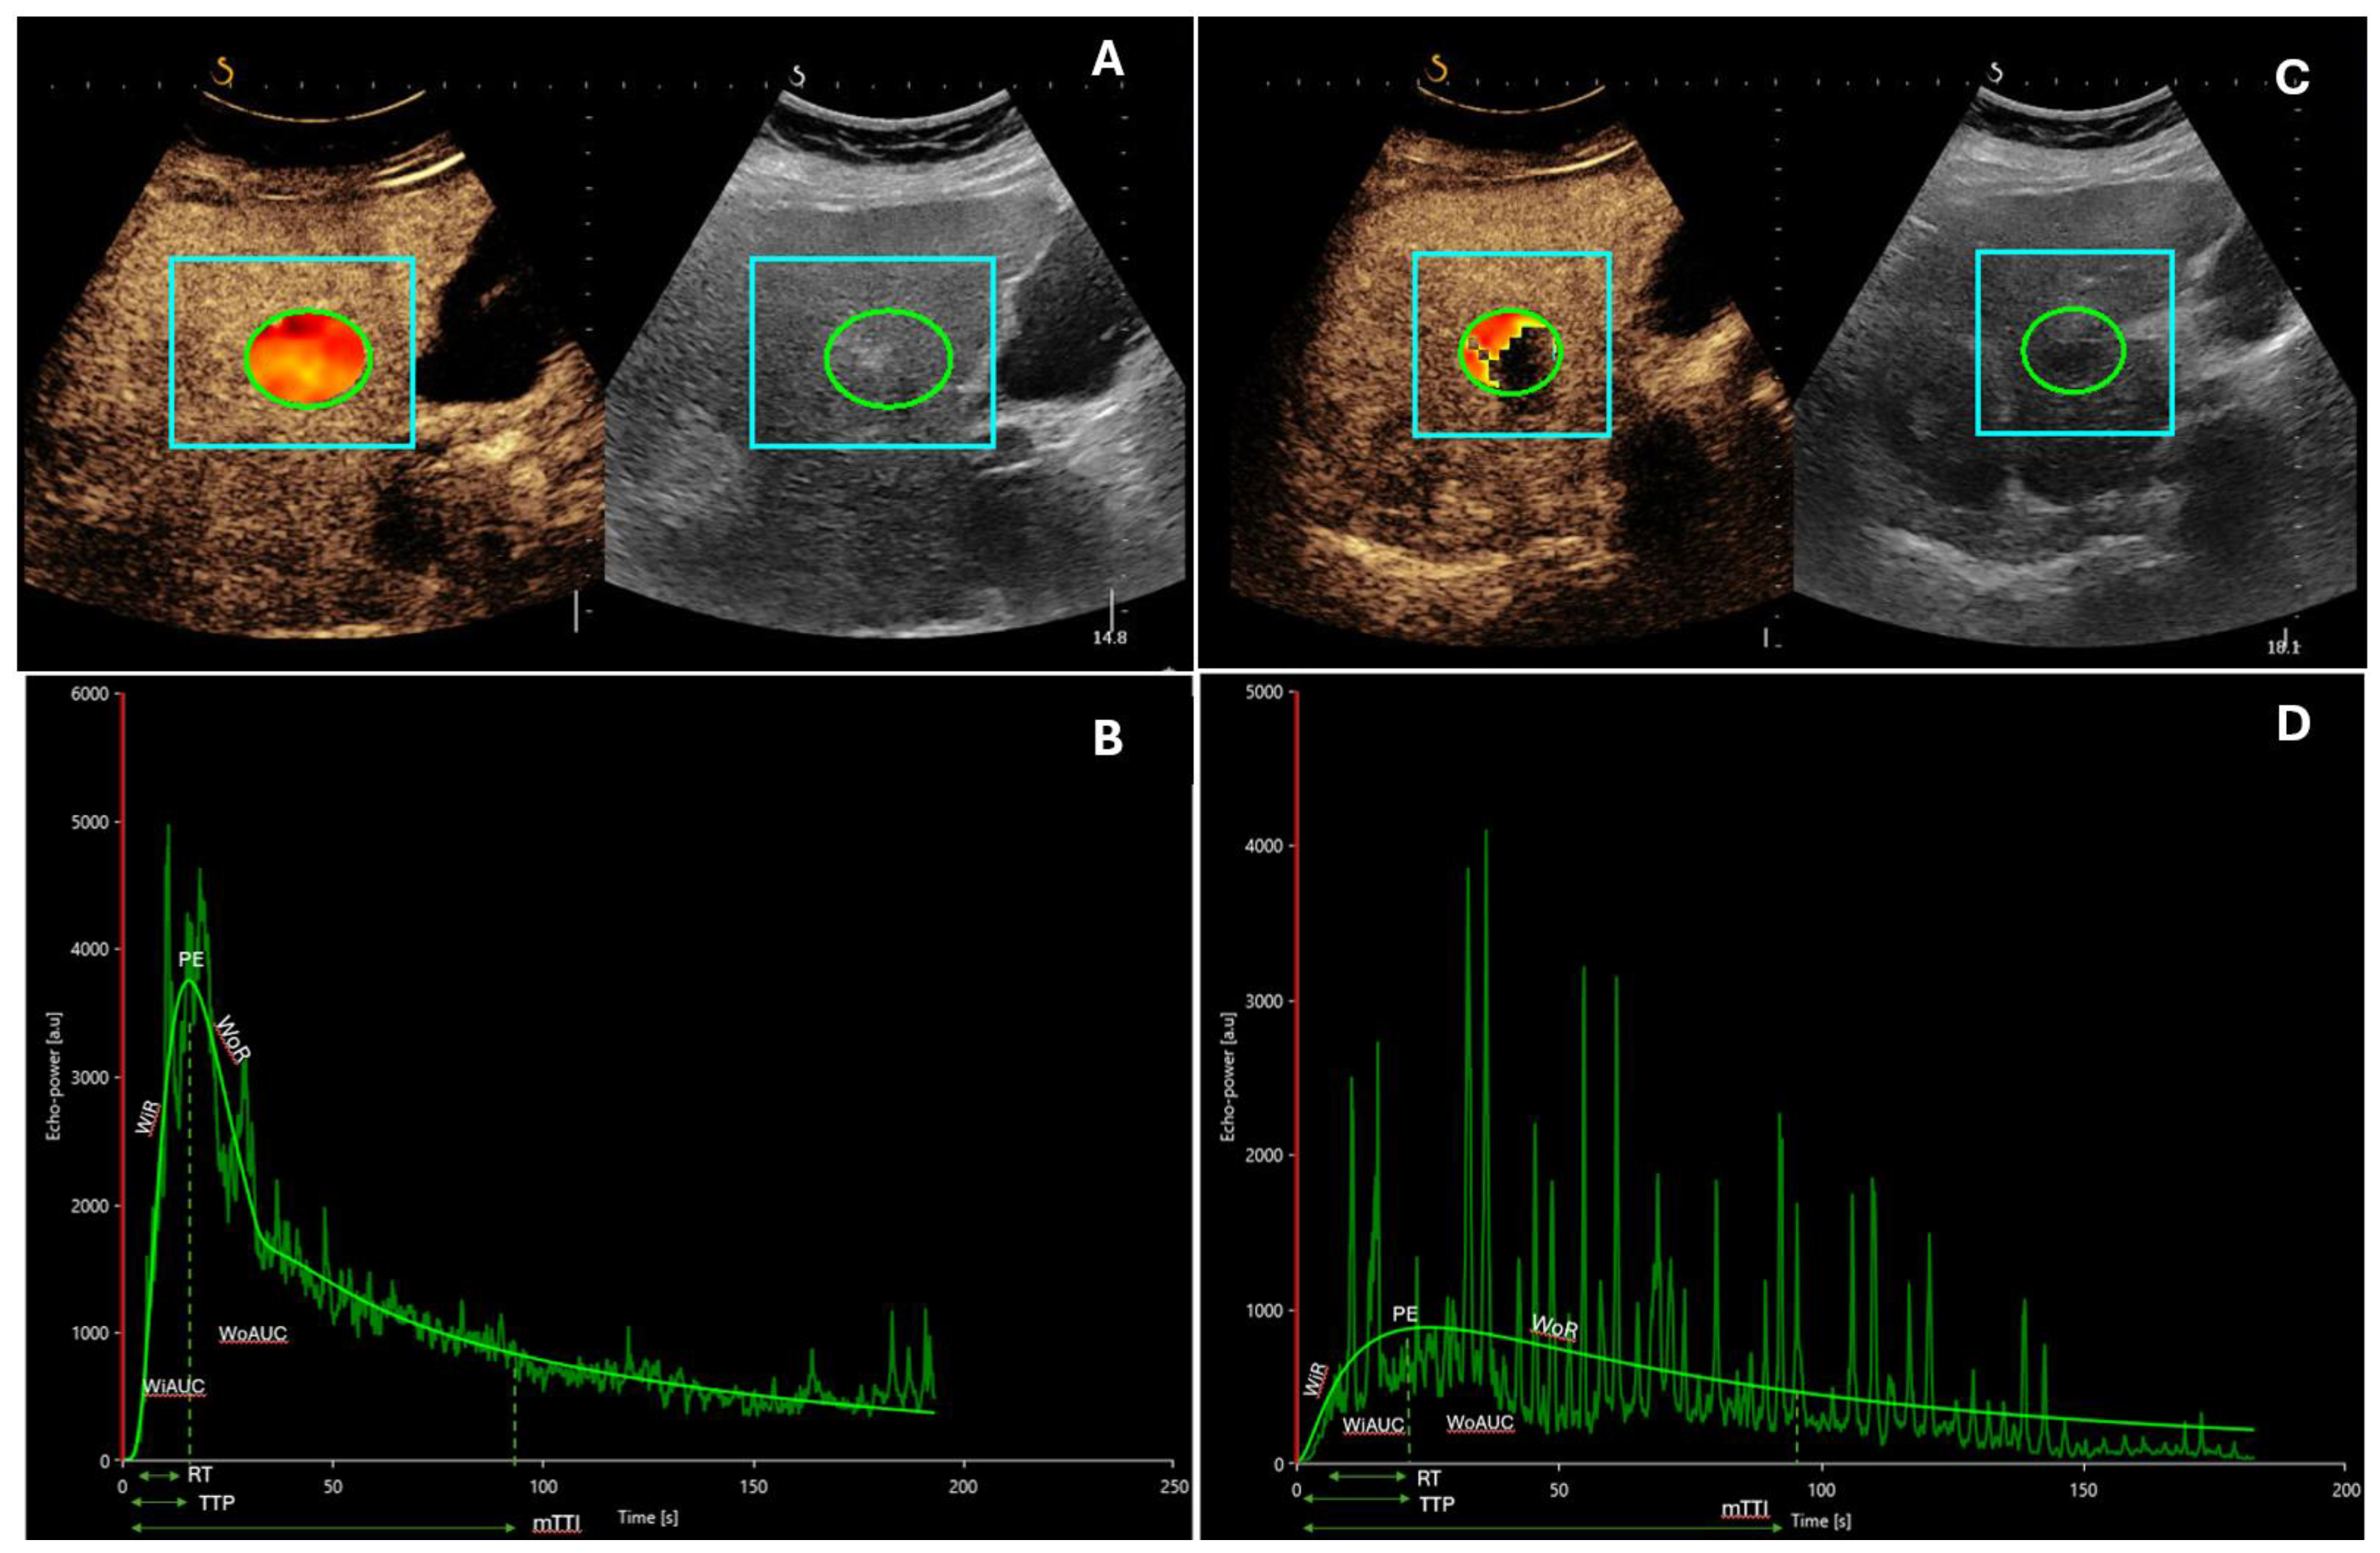

- Zocco, M.A.; Garcovich, M.; Lupascu, A.; Di Stasio, E.; Roccarina, D.; Annicchiarico, B.E.; Riccardi, L.; Ainora, M.E.; Ponziani, F.; Caracciolo, G.; et al. Early Prediction of Response to Sorafenib in Patients with Advanced Hepatocellular Carcinoma: The Role of Dynamic Contrast Enhanced Ultrasound. J. Hepatol. 2013, 59, 1014–1021. [Google Scholar] [CrossRef] [PubMed]

| Zocco [34] | 28 | SonoVue®, Bracco, Italy | Sorafenib | Mean overall survival (OS): responders > non-responders (382 versus 158 days; p = 0.003) Decrease at 15 and 30 days: peak-intensity (PI; p < 0.001), time to PI (Pw; p = 0.003), area under the curve (AUC; p = 0.002) Correlation between performance free survival (PFS), Pw, Tp, AUC |